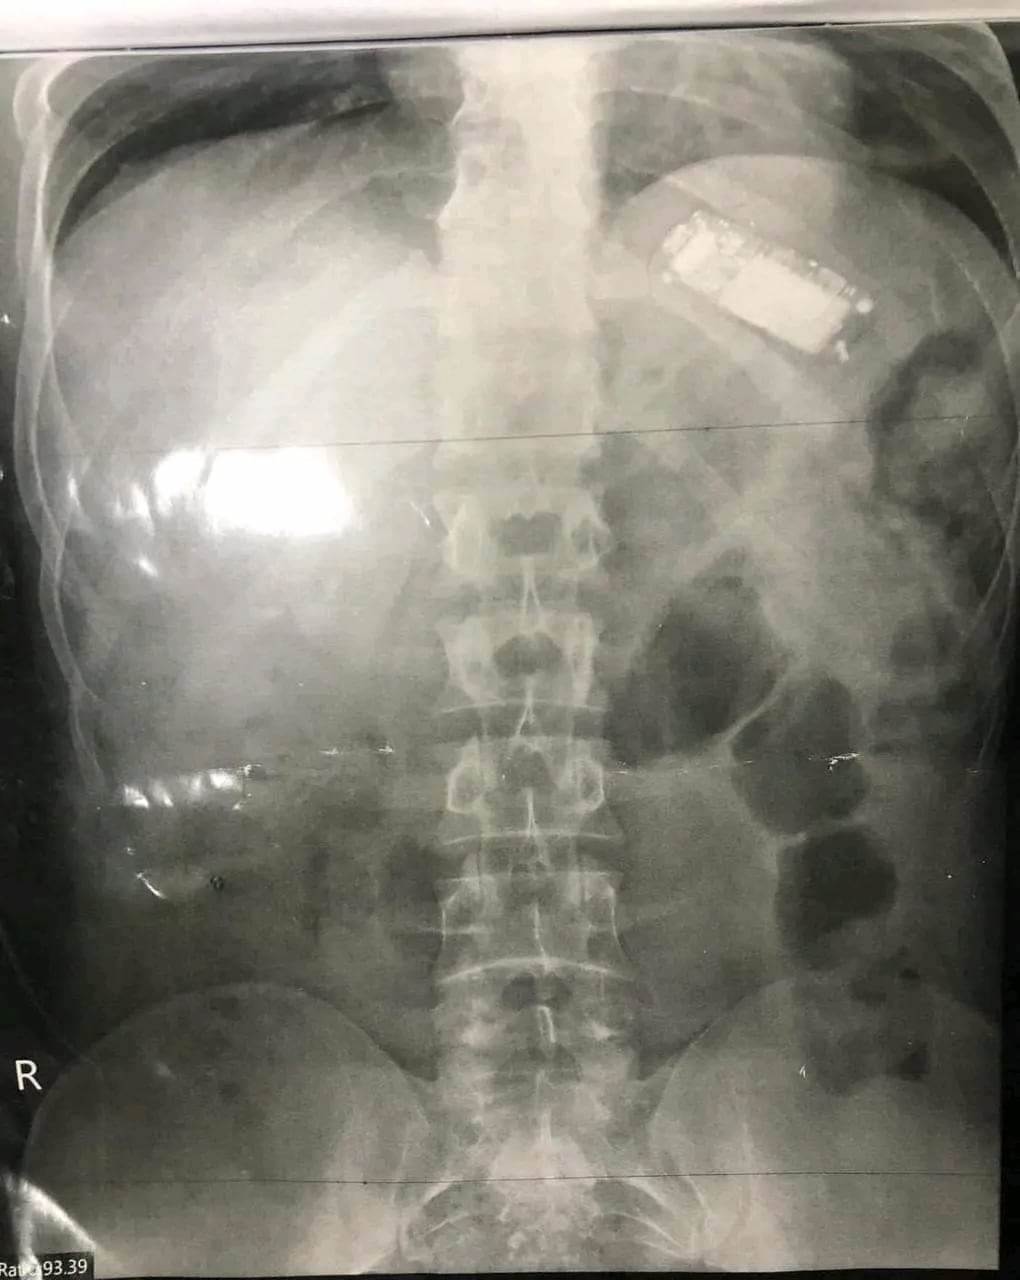

نجح فريق طبي بمستشفى الباطنة التخصصي بجامعة المنصورة، في استخراج هاتف محمول من معدة شاب في العقد الثالث من عمره بعدما ابتلعه منذ شهرين، وذلك باستخدام المنظار.

واستقبل شاب يبلغ من العمر 23 عامًا، يعاني من آلام في المعدة وفقدان في الوزن، وأخبر الأطباء أنه ابتلع هاتفًا محمولًا منذ شهرين، وتدهورت حالته الصحية.

وعلى الفور وجه الدكتور حازم حكيم، مدير مستشفى الباطنة التخصصي، بإجراء الفحوصات الطبية اللازمة من أشعة وتحاليل للمريض، تحت إشراف الدكتورة أسماء جميل، مدرس واستشاري الكبد والجهاز الهضمي والمناظير، وتم اكتشاف وجود الهاتف المحمول داخل بطنه.